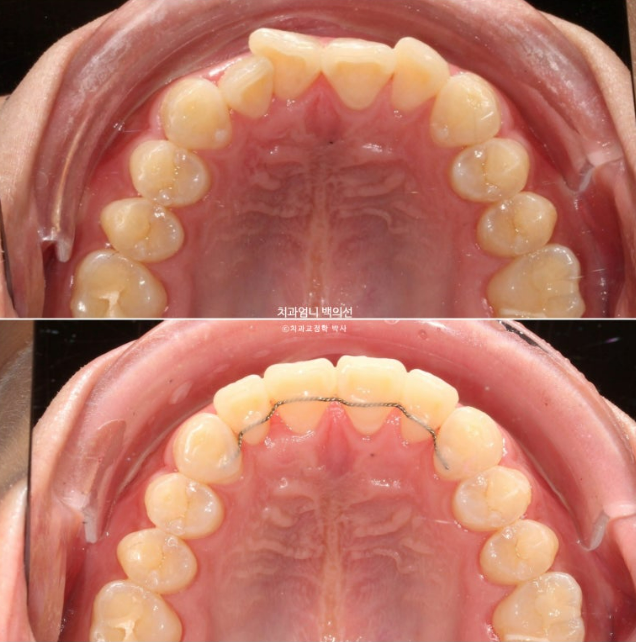

25년 6월, 5개월만에 치료를 마무리 했습니다.

25.06

문제의 앞니 끝단 모양을 조금 다듬어 마모된 부분이 티가 덜나게 해드렸습니다.

원래 좋았던 교합은 잘 유지가 되었습니다.

유지장치까지 들어간 모습입니다.